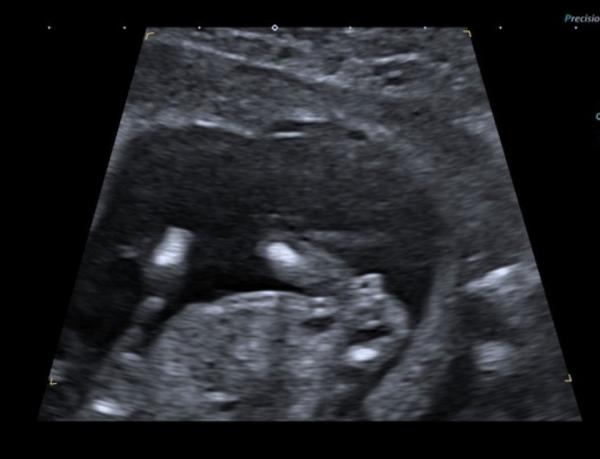

Hallo :) Ich bin aktuell in der 15. SSW und war vor wenigen Tagen bei dem Ersttrimesterscreening.  Mich würde interessieren, was ihr über das Geschlecht sagt, da meine Frauenärztin sich noch nicht ganz sicher war :) Natürlich ist es dann schwierig, hier das Geschlecht zu bestimmen aber neugierig bin ich trotzdem über Meinungen.  Wir würden uns über beides freuen und sind einfach zu ungeduldig, um noch 6 Wochen auf den nächsten Termin zu warten :) Ein NIPTtest wurde nicht gemacht, da es keine Indikation dafür gab.  Vielen Dank und liebe Grüße

Bild zu Vermutungen Jung oder Mädchen ? - Schwanger - wer noch? Rund um die Schwangerschaft